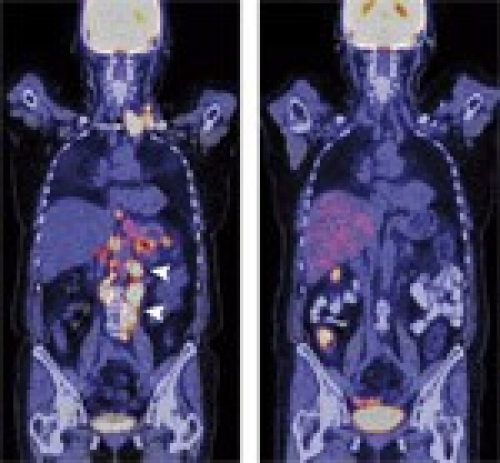

Palliative first-line therapy with weekly high-dose 5-fluorouracil and sodium folinic acid as a 24-hour infusion (AIO regimen) combined with weekly irinotecan in patients with metastatic adenocarcinoma of the stomach or esophagogastric junction followed by secondary metastatic resection after downsizing

Kathrin Koucky, Axel Wein

DOI: 10.12659/MSM.881764

Med Sci Monit 2011; 17(5): CR248-258

Kathrin Koucky, Axel Wein, Peter C. Konturek, Heinz Albrecht, Udo Reulbach, Gudrun Mannlein, Kerstin Wolff, Nicola Ostermeier, Dagmar Busse, Henriette Golcher, Claus Schildberg, Rolf Janka, Werner Hohenberger, Eckhart G. Hahn, Jurgen Siebler, Markus F. Neurath, Frank Boxberger